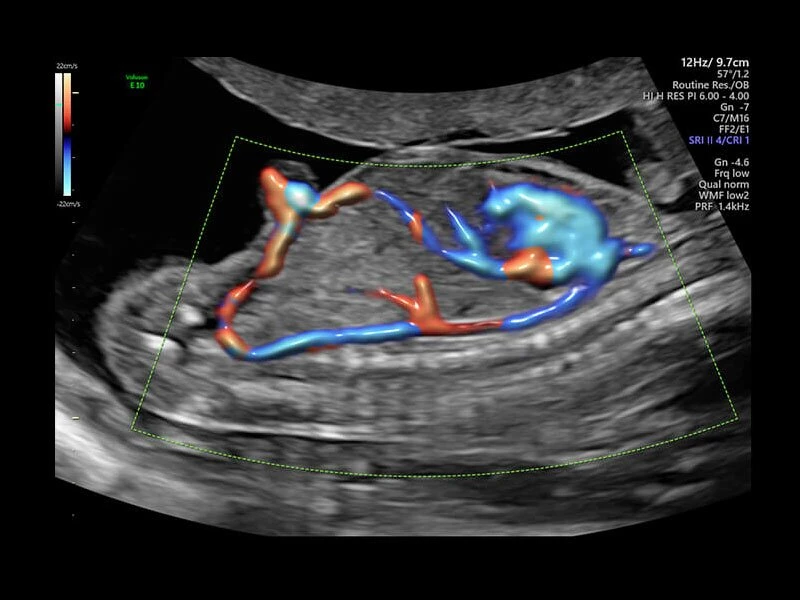

Она оснащена инструментами, которые упрощают получение изображений, отличается высокой чувствительностью цветового допплера, поддерживает инновационные 3D/4D технологии.

Voluson E10 поддерживает инновационные технологии формирования изображений — HDlive Silhouette и HDlive Flow, которые позволяют увидеть мельчайшие детали. Алгоритм SonoRenderlive упрощает рабочий процесс и дает возможность реконструировать изображение поверхностей, определяя область перехода между тканью и жидкостью.

- Технология HDlive Flow — повышает реалистичность визуализации сосудистых структур, улучшая восприятие глубины (по сравнению с традиционным цветовым допплером и функцией HD-Flow).

- HD-flow или, так называемый, высокочувствительный тканевый допплер.

- Позволяющая визуализировать плод в объеме стандартная программа HD-live с дополнительным приложением Hdlive Silhouette, включающим в себя режим «Силуэт», с помощью которого можно выделять границы тканей, контуры объектов. В этот же пакет входит и режим HDlive Flow, представляющий из себя источник света, перемещаемый и совместимый с режимом визуализации тока крови в объеме.

- Возможность визуализации тока крови в B-Flow (недопплеровский режим).